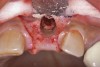

(17.) A cross-linked collagen bone graft scaffold is applied over the debrided implant surfaces to help reconstruct a portion of the deficient buccal bone.

Figure 17

(18.) A subepithelial, connective tissue graft from the palate is affixed over the collagen bone scaffold and around the abutments of the three involved implants.

Figure 18